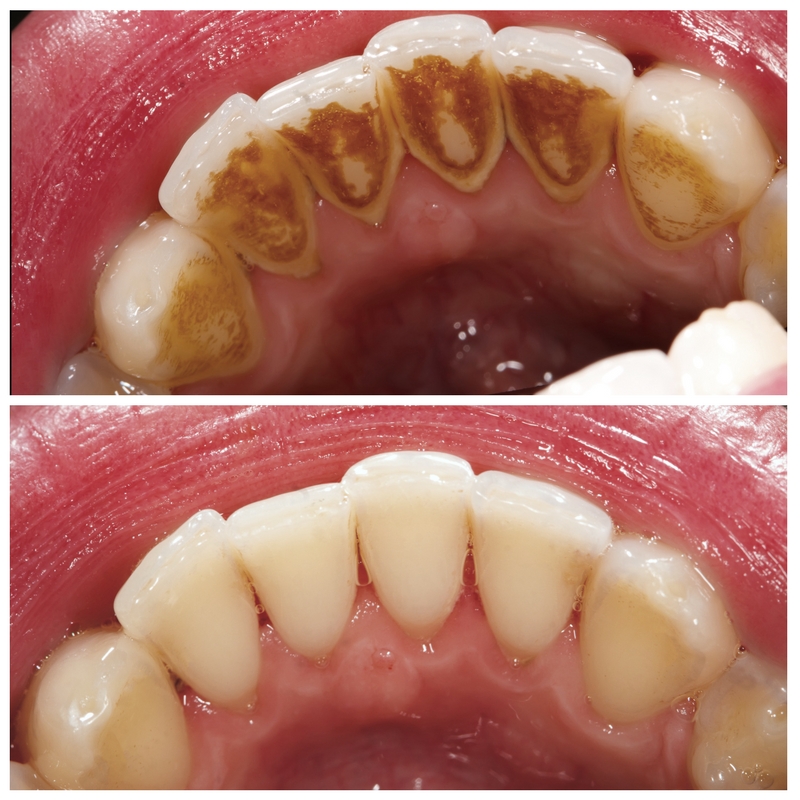

Teeth cleaning is a professional dental procedure that involves the removal of plaque, tartar, and stains from the teeth...

Teeth scaling, also known as dental scaling, is a professional dental procedure that involves the thorough removal...